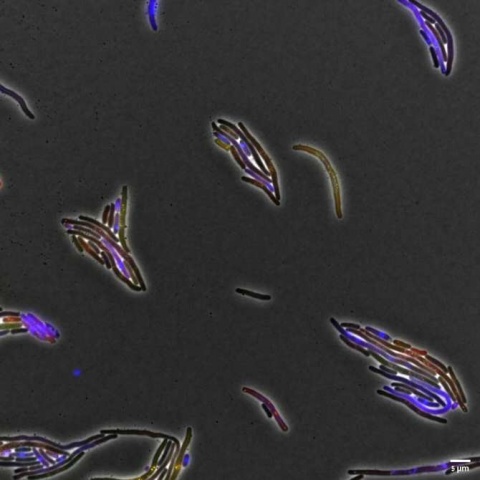

Nanovehículos de sílice para la liberación controlada de L-dopa como potencial tratamiento alternativo de la enfermedad del Parkinson. (Imagen: V. Morales, J. McConnell, M. Pérez-Garnes, N. Almendro, R. Sanz, R. A. García-Muñoz: “l-Dopa release from mesoporous silica nanoparticles engineered through the concept of drug-structure-directing agents for Parkinson's disease”. Journal of Materials Chemistry B, 2021)